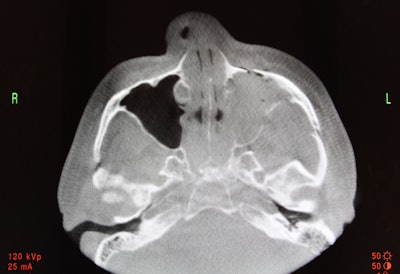

Preoperative CT scan (above) shows a left-sided zygomaticomaxillary complex fracture that is moderately displaced and rotated. After sublabial access and mobilization, reduction is confirmed with intraoperative CT (below). Reduction has been achieved and no further incisions are necessary.